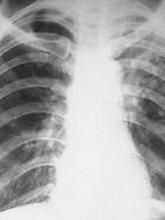

1.哮喘型X線胸片見有程度不等的肺過度充氣征。

2.支氣管炎型X線胸片常呈肺紋理增強,有報導出現此征者達60%,部分也可有沿肺紋走向的小片陰影。

3.肺炎型X線胸片表現有沿肺紋走向的斑點狀或小片狀類似支氣管性肺炎的陰影,或呈節段性或大葉性邊緣不清的陰影,可多發或單發,下野較多見,此型易誤診為細菌性肺炎,但抗炎治療無效,抗瘧治療2~3天后臨床症狀及X線胸片表現均有明顯好轉。

4.肺水腫型X線胸片示兩肺紋理增粗模糊、以肺門為中心的蝴蝶狀陰影及兩肺中下野不對稱的大片狀可隨體位不同而變動的陰影等改變。